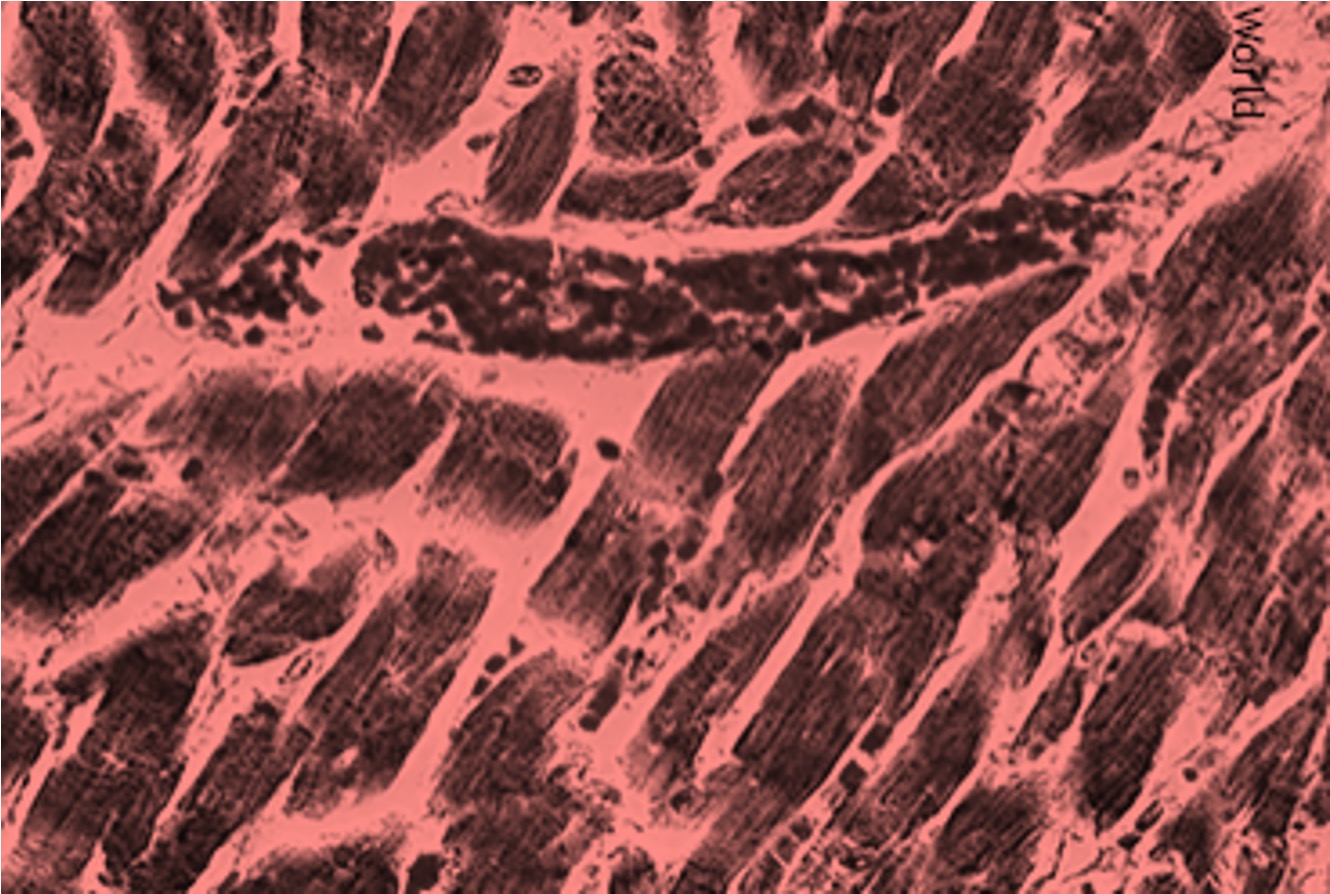

Our mission is to advance a novel cardiac myosin inhibitor that can improve the treatment of [obstructive] hypertrophic cardiomyopathy by reducing patients’ symptoms rapidly and preserving patients’ ability to live active lives.

Our approach is rooted in a deep understanding of HCM. We leverage advanced research and clinical development to bring forward a novel cardiac myosin inhibitor with the potential to significantly improve patient outcomes and enhance their quality

of life.

Our lead asset, BH-1893, was engineered for properties that may offer practical advantages to current therapies. In data to date, BH-1893 has demonstrated it can reduce the blockage in the heart, leading to improved blood flow and reduced symptom; is generally well-tolerated with manageable side effects; and begins working quickly, with some patients experiencing improvement within weeks. These characteristics, if confirmed in late-stage trials, could make treatment more accessible and convenient for patients.